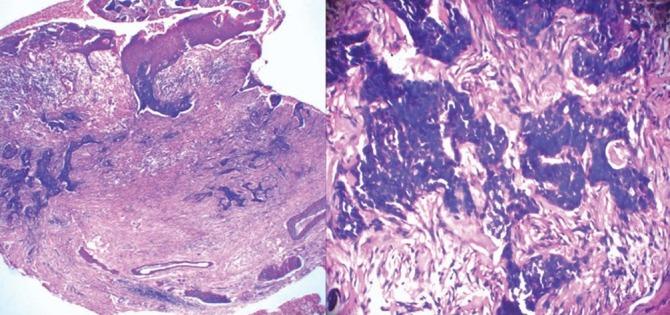

Sebaceous carcinoma is a rare neoplasm of the sebaceous gland. It is diagnosed mainly on histopathology and, clinically, it may mimic other neoplasms like squamous or basal cell carcinoma. We came across a patient presenting with a non-healing ulcer over the left temporo-parietal region of the scalp since 4 years and a single asymptomatic nodule over the occipital region since 3 years. Histopathology from an ulcer was pathognomonic of sebaceous carcinoma and that from a nodule was suggestive of proliferating trichilemmal cyst. The patient was screened for Muir Torre syndrome. We referred the patient to the oncologist for further management, where the patient was advised complete excision of the lesion.

皮脂腺癌是一种罕见的皮脂腺肿瘤。其诊断主要依靠组织病理学,在临床上,它可能会与其他肿瘤相似,如鳞状细胞癌或基底细胞癌。我们遇到一位患者,其头皮左颞顶区有一个4年未愈合的溃疡,枕部有一个3年的无症状结节。溃疡部位的组织病理学表现为皮脂腺癌的特征性表现,结节部位的组织病理学提示为增生性外毛根鞘囊肿。对该患者进行了穆尔-托里综合征的筛查。我们将患者转诊给肿瘤学家进行进一步治疗,肿瘤学家建议对病变进行完整切除。